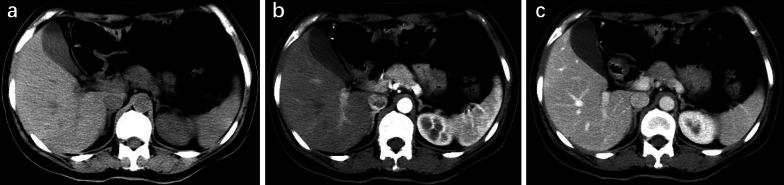

Patients with pancreatic MiNEN more frequently presented with large size and heterogeneous and cystic components compared with PDAC (p < 0.031) and ill-defined irregular margins, progressive enhancement, and adjacent organ involvement compared with NET (p < 0.036). However, vascular invasion was less commonly seen in MiNEN than PDAC (p = 0.010). Moderate enhancement was observed more frequently in MiNEN than in PDAC or NET (p < 0.001). Multivariate logistic analyses demonstrated that moderate enhancement and ill-defined irregular margin were the most valuable features for the prediction of pancreatic MiNEN (p ≤ 0.044). The combination of the two features resulted in a specificity of 93.8%, sensitivity of 83.3%, and accuracy of 91.7%.

We have mainly described the radiological findings of pancreatic MiNEN with ill-defined irregular margin and moderate enhancement compared with PDAC and NET. The combination of imaging features could improve diagnostic efficiency and help in the selection of the correct treatment method.